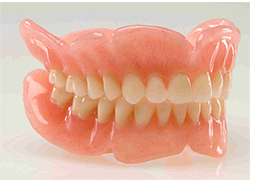

La prótesis dental son dientes artificiales que se emplean cuando se ha perdido una, varias o todas sus piezas dentales.

La prótesis dental son dientes artificiales que se emplean cuando se ha perdido una, varias o todas sus piezas dentales.

Caries profundas, problemas de encía, accidentes o fracturas obligan al odontólogo a extirpar la o las piezas dañadas o con la edad se van deteriorando y aflojando de tal forma que se caen solas.

Gracias a los avances de la tecnología, ahora ya que pueden ofrecer diversas opciones a los pacientes para recuperar de forma “postiza o artificial”, su dentadura.

Lo que si bien no es igual a tener la dentadura propia, ayuda sin duda a que la boca realice sus funciones de forma casi normal. Cuando se han perdido todas las piezas dentarias de un maxilar o de los dos, las personas tienen dos opciones: o utilizar dentaduras completas móviles o aplicarse implantes para colocar los dientes de forma definitiva.